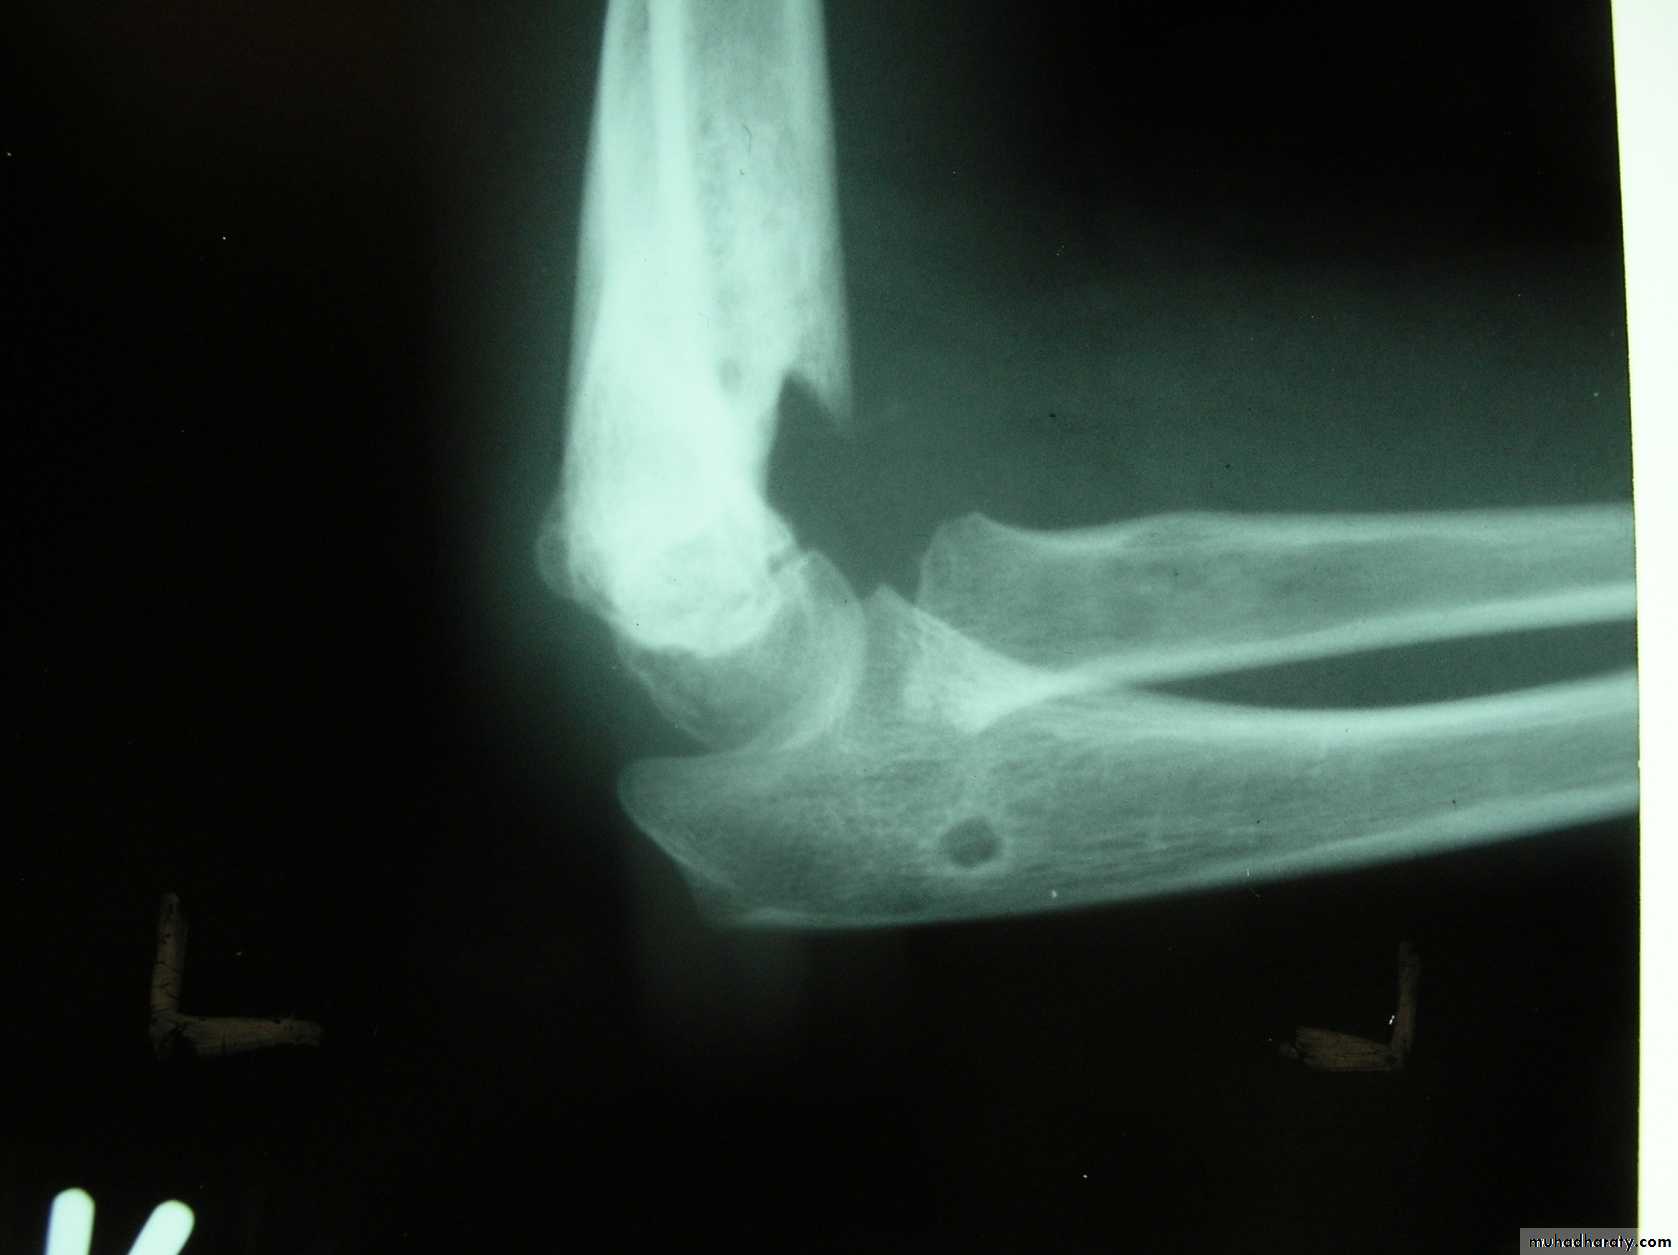

Is this a simple extension

type supracondylar fracture ??

It also has

anterolatateraldisplacement !!

The distal fragment is

not flexed,but also it is not extended to any degree.

This also is a Type III Flexion Pattern.

But, if not recognized as such, it may be a problem.

This fracture was irreducible,